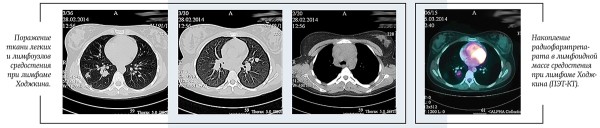

В настоящее время стандартом обследования при ЛХ является позитронно-эмиссионная томография с 18F-флюородезокси-глюкозой, совмещенная с КТ (ПЭТ-КТ).

ПЭТ-КТ позволяет точнее определить вовлеченные в опухолевый процесс лимфатические узлы и области организма, определить стадию и объем лечения. В нашей стране данный метод стал доступен для всех пациентов с ЛХ с 2017 года.

С активным внедрением ПЭТ-КТ в диагностику лимфом началась новая эра в лечении детей с ЛХ. ПЭТ-КТ стала активно применяться не только для стадирования, но и для оценки статуса ремиссии и раннего ответа на терапию. Быстрое достижение ПЭТ-негативности является маркером чувствительности опухоли к химиотерапии. Появился способ выявлять пациентов, для которых возможно отказаться от ЛТ. С 2017 года ЛТ отменяют пациентам с ранними стадиями, достигшим полной ремиссии по данным ПЭТ-КТ после завершения этапа ПХТ.

ПЭТ-КТ: в переднем средостении верхнего этажа срединно с акцентом вправо опухолевая масса; 36ґ73ґ60 мм. Изолированно лежащие увеличенные лимфоузлы: паратрахеальные и бифуркационные, до 15 мм; парастернально справа, до 18 мм. По данным ПЭТ: накопление РФП помимо вышеописанных узлов — в правом корне (бронхопульмональные л/узлы), в л/узлах — прекардиально справа, в кардиодиафрагмальной области слева, параэзофагеально (на КТ узел, 14 мм).

Очагов патологической плотности в легочной паренхиме не выявлено. Легочной рисунок не изменен. Долевые и сегментарные бронхи проходимы. Корни легких не расширены, структурны. Подмышечные л/узлы не увеличены. Плевральные полости свободны. Мягкие и костные ткани грудной клетки без структурных изменений. Отмечается увеличение забрюшинных л/узлов, до 23 мм; общих подвздошных до 15 мм. На ПЭТ патологическое накопление РФП помимо вышеописанных узлов — в воротах печени, в наружных подвздошных л/узлах, в селезенке.

Патологических объемных образований в брюшной полости и забрюшинном пространстве не выявлено. Печень не увеличена, однородной структуры. Поджелудочная железа гомогенна, обычных размеров и положения. Почки без видимых изменений.

В левой подвздошной кости определяется очаг гиперденсивной плотности с мелкобугристыми контурами, размером 10,5ґ6,6 мм. На ПЭТ также отмечается повышенное накопление РФП в телах позвонков С6, Тн4, L5, S1; ребрах; костях таза.

Заключение: лимфопролиферативное заболевание с поражением лимфоузлов по обе стороны диафрагмы, селезенки, костей.

Получен полный метаболический ответ по данным ПЭТ-КТ после этапа ПХТ. С целью консолидации ремиссии проведена лучевая терапия на зоны инициального поражения в СОД=20 Гр.